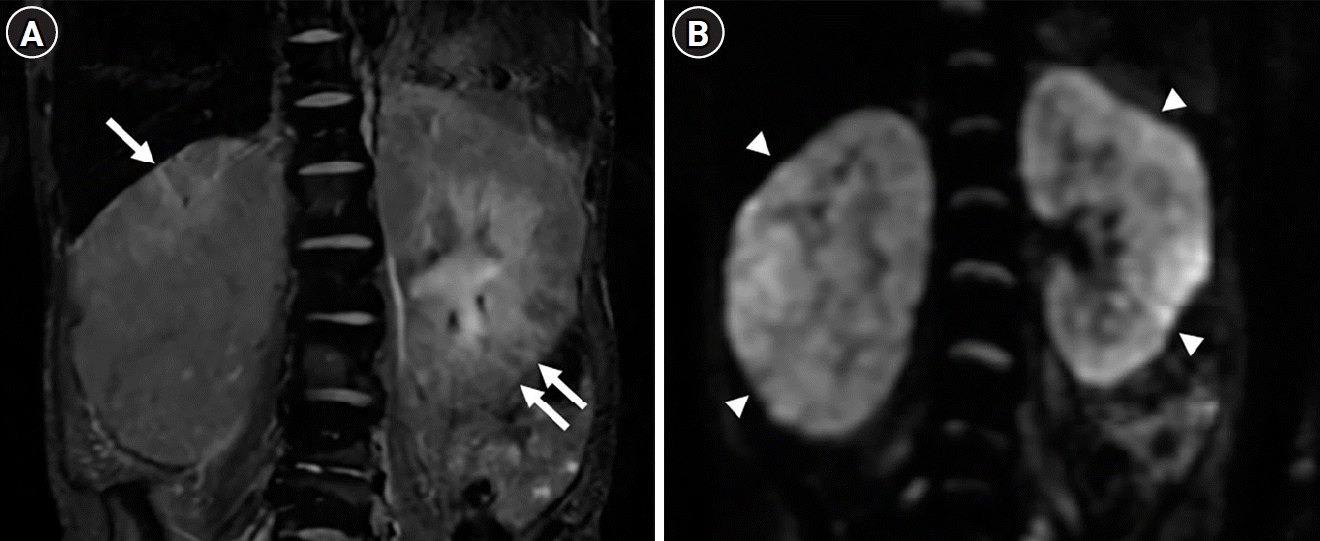

Fig. 2.

Axial unenhanced abdominal computed tomography (CT) image (A) and axial (B) and coronal (C) contrast-enhanced abdominal CT images during the 70-second delayed portal venous phase at the time of referral to the nephrology department show diffuse enlargement of both kidneys. In the axial unenhanced abdominal CT image (A), the attenuation of both kidneys is unevenly increased (arrows) despite the absence of contrast material usage in the near past. Both axial (B) and coronal (C) contrast-enhanced CT images show relatively homogeneous enhancement of both renal cortices, but with slightly decreased enhancement compared to normal brisk renal cortical enhancement. Bilateral perirenal fat infiltration is observed, but there is no striated nephrogram that would suggest pyelonephritis. Although right hydronephrosis is noted, there is no significant change compared to 3 months ago and no unilateral delayed nephrogram.

Fig. 3.

A coronal fat-suppressed T2-weighted magnetic resonance image (A) displays diffuse enlargement of both kidneys with multiple wedge-shaped hyperintense areas in the renal parenchyma (arrows). A coronal diffusion-weighted whole-body image (B) shows hyperintensity in both kidneys (arrowheads), indicating diffusion restriction.